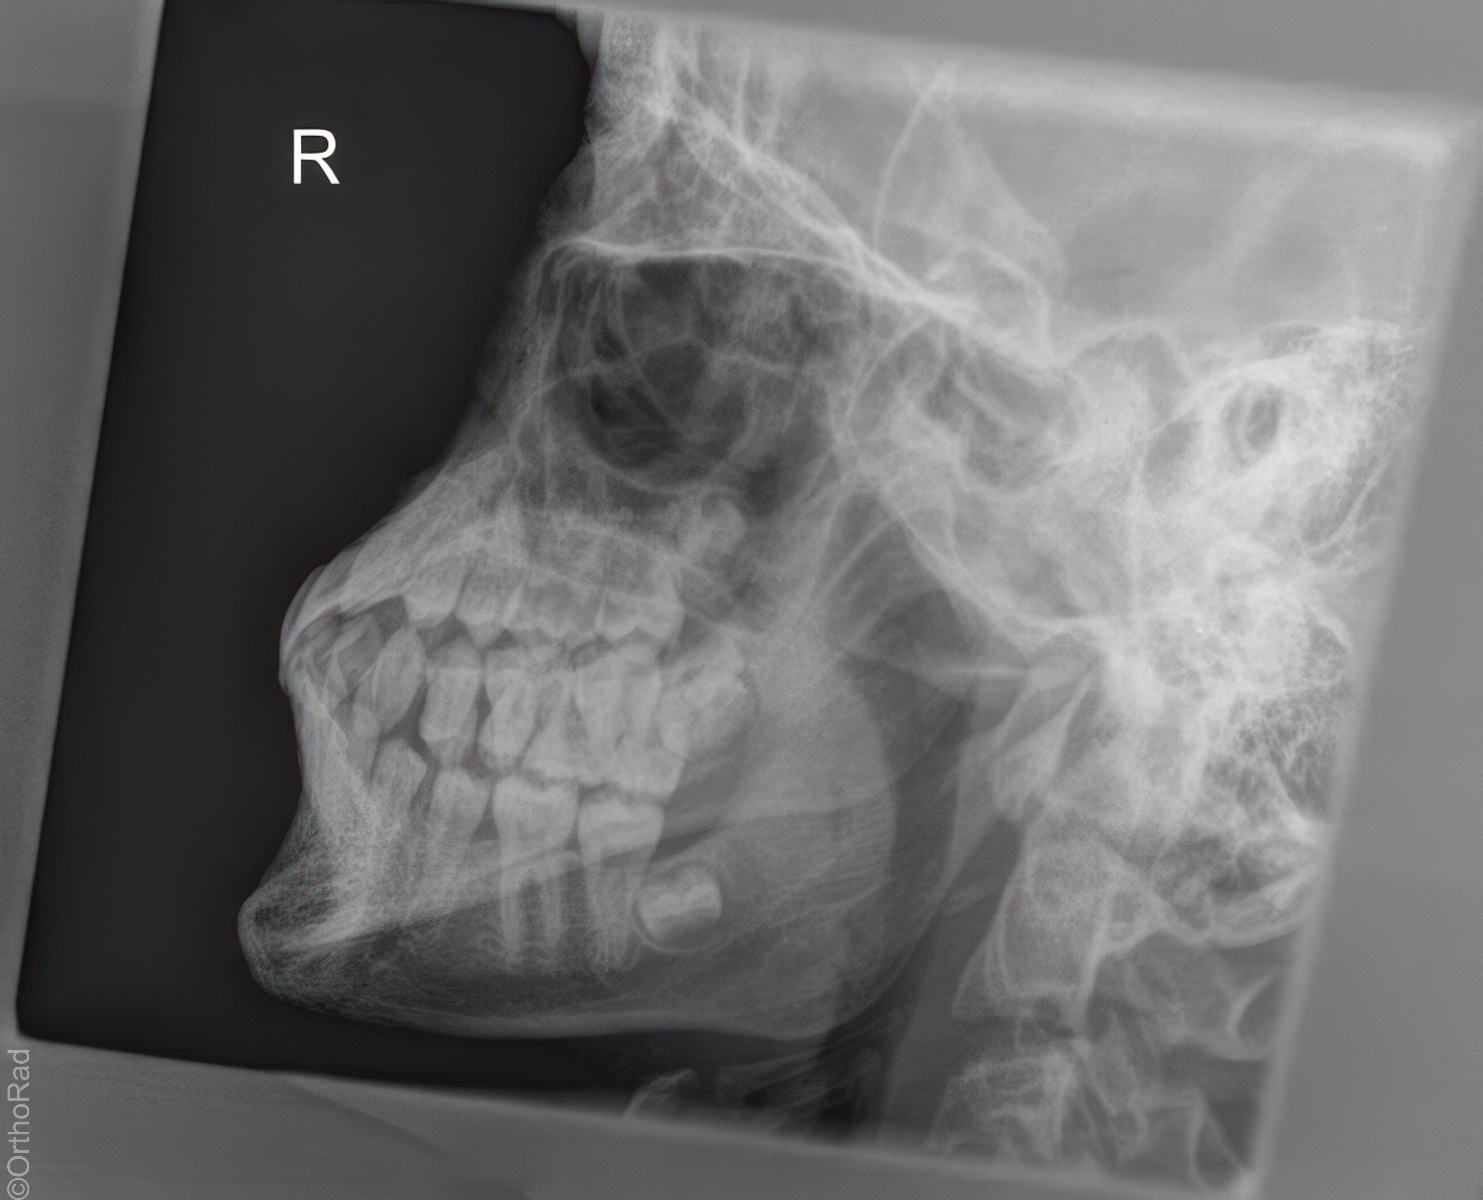

Schädel lateral

Lagerung

Schräg-Bauchlage mit aufstützender Hand der anliegenden Schädelseite

Beine leicht angezogen

Kopf streng seitlich

Medianebene parallel zum Tisch

Kinn und Stirn auf einer gedachten Linie (D.-H. nicht relevant)

Qualitätskriterien

Vollständige Darstellung des gesamten Schädels, weitgehend deckend der Konturen, vordere und hintere Schädelgrube, Orbita, Kieferhöhlen und Jochbein. Zudem deckungsgleich von kleiner Keilbeinflügel und äußerer Gehörgang. Strichförmige Abbildung der Sella turcica.